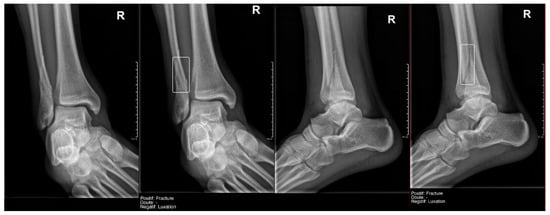

- Ankle and foot: On six occasions, Milvue marked the fracture variable as doubtful in cases with a bipartite medial sesamoid (two patients), an accessory sesamoid at the base of the 5th metatarsal, synphalangism, os peroneum, and os naviculare. (Figure 8).